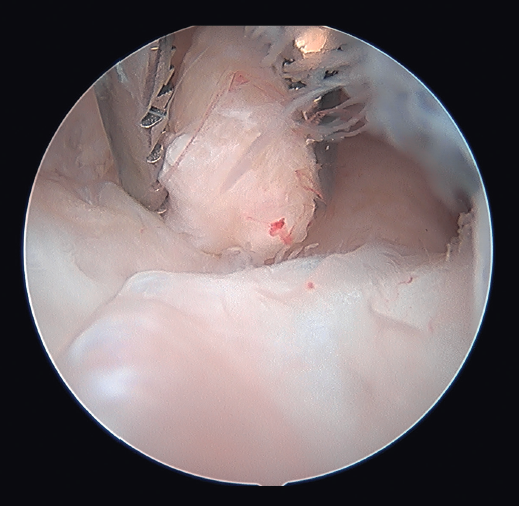

Técnica quirúrgica de la artrólisis artroscópica en un codo postraumático

La técnica es similar a la descrita por O’Driscoll o Pederzini(19,22) bajo anestesia plexual. Con el paciente colocado en decúbito lateral y con manguito de isquemia en la raíz del miembro, este se coloca en un soporte que permite que el hombro esté a 90° de abducción y el codo a 90° de flexión. Se marcan las referencias (Figura 1) (ambos epicóndilos, olécranon, tendón del tríceps, septo intermuscular medial, cúpula radial y soft spot) y, si se dan las condiciones explicadas previamente, se libera el nervio cubital a través de un abordaje posteromedial de escasos 3 cm que permite liberar por completo y movilizar al nervio para realizar el portal proximal medial con seguridad (Figura 2) y, en caso de déficit de flexión, seccionar la banda posterior del ligamento colateral medial. Una vez liberado el nervio, se insuflan entre 20 y 40 cc de suero salino fisiológico a través del soft spot (centro del triángulo formado por el epicóndilo lateral, la cúpula radial y el olécranon) para distender la articulación y disminuir el riesgo de lesión neurovascular(23). En caso de tener que trabajar en el compartimento posterior por adherencias tricipitales o capsulares que impidan la flexión o por ocupación de la fosa olecraneana por fibrosis o cuerpos libres que impidan la extensión (Figura 3), hay autores que defienden iniciar la artroscopia por la cámara posterior para evitar el edema que aparece en las partes blandas posteriores durante el trabajo en la cámara anterior que dificulta el trabajo final en la cámara posterior(19,22). En este caso, realizaremos 2 portales posterolaterales o un portal directo en el soft spot y otro posterolateral que nos permitan buena visión, seguir la gotiera lateral en sentido proximal y realizar exéresis del tejido que esté ocupando la fosa olecraneana, resecar la punta del olécranon si fuera necesario y el tejido cicatricial de la gotiera lateral y de la articulación radiocubital proximal posterior (Figura 4) y despegar el tríceps del húmero si existieran adherencias. En el compartimento posterior en algunos casos (codos de pequeño tamaño, gran ocupación de espacio) puede ser útil emplear la óptica de pequeñas articulaciones, aunque en la gran mayoría de los pacientes se puede usar el artroscopio de 4,5 mm y 30°.